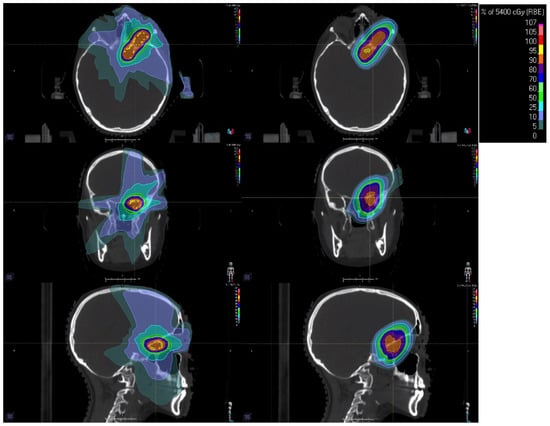

4.2. Hippocampal-Sparing Technique

- Gondi, V.; Tolakanahalli, R.; Mehta, M.P.; Tewatia, D.; Rowley, H.; Kuo, J.S.; Khuntia, D.; Tomé, W.A. Hippocampal-Sparing Whole-Brain Radiotherapy: A “How-To” Technique Using Helical Tomotherapy and Linear Accelerator–Based Intensity-Modulated Radiotherapy. Int. J. Radiat. Oncol. 2010, 78, 1244–1252. [Google Scholar] [CrossRef]